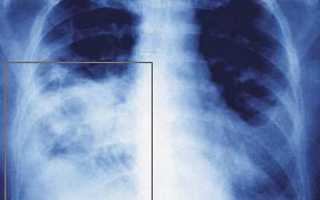

Рентгенограмма при пневмонии нижней доли правого легкого